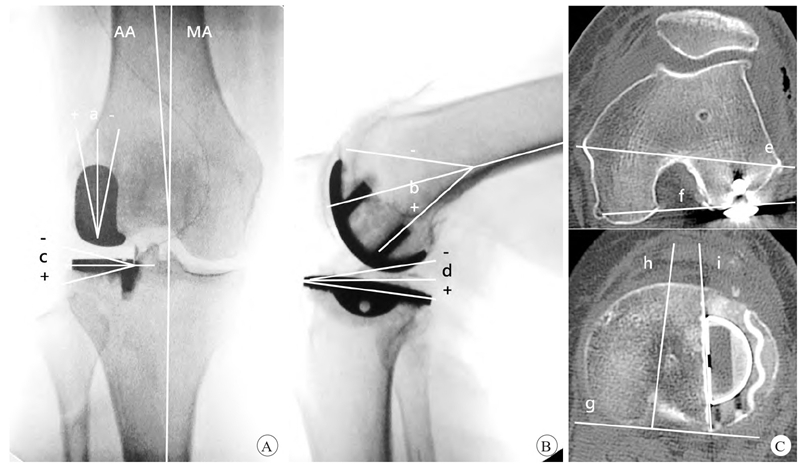

图2 UKA假体力线测量方法示意

A.冠状位假体力线(a为股骨侧,+为外翻,−为内翻,c为胫骨侧,AA为解剖轴,MA为机械轴);B.矢状位假体力线(b为股骨侧,+为后倾,−为前倾,d为胫骨侧);C.假体旋转力线(e为股骨内外上髁连线,f为外侧后髁股骨假体力线,e、f夹角为股骨假体旋转角,−为内旋,指f线相对于e线内旋,+为外旋,指f线相对于e线外旋,g为胫骨平台后缘切线,h为胫骨平台前后轴,i为胫骨假体的外侧缘,h、i夹角为胫骨假体旋转角,−为内旋,指i线相对于h线内旋,+为外旋,指i线相对于h线外旋)。